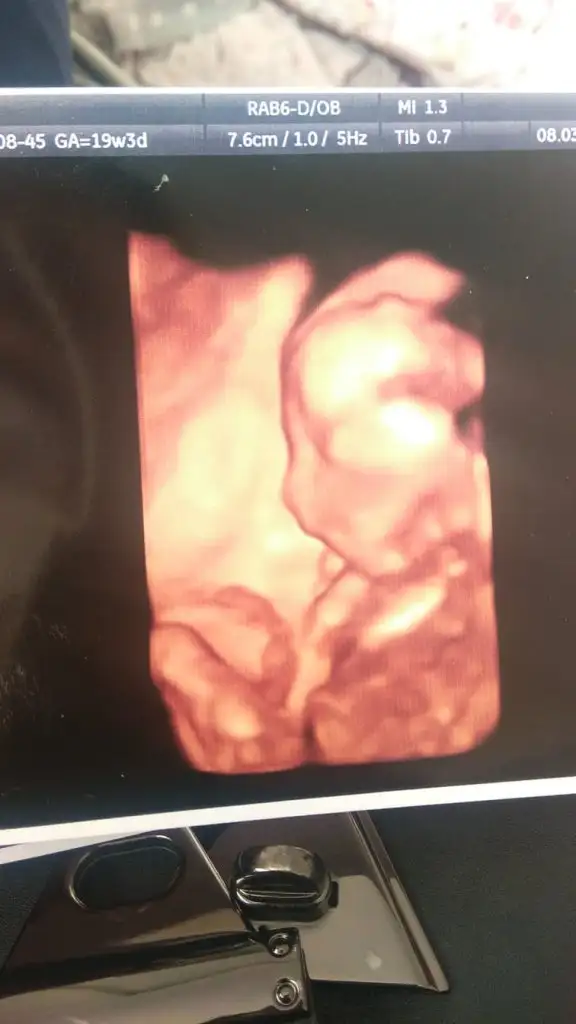

En iyi 11 12 13 haftalar olmalıIkra meyra kardeşimin 19 haftalik doktor söylemedi anlaşılıyor mu cinsiyeti